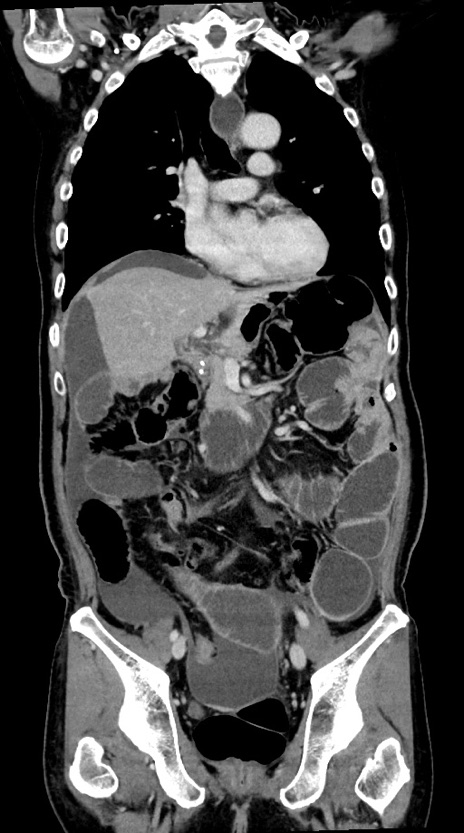

症例28(冠状断像)

【症例】60歳代男性

【主訴】嘔吐

【現病歴】胃癌にて胃全摘後。食思不振が悪化し、夜中に嘔吐することがある。

【既往歴】胃癌、胃全摘、脾摘、胆摘後

【データ】WBC 5900、CRP 10.56